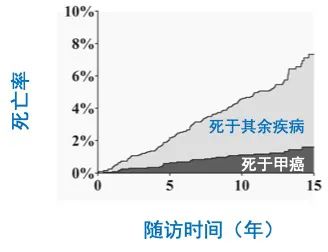

甲状腺是人体中非常重要的内分泌器官,外形像一只美丽的蝴蝶,通过分泌甲状腺激素促进物质和能量的代谢,对人体的多系统具有重要影响。近年来,随着人们体检意识的增强和超声诊疗技术的迅猛发展,甲状腺恶性结节的检出率呈逐年增高的趋势,而一旦确诊,颈部这只美丽的蝴蝶就面临着折翼的风险——外科手术切除。腺体切除、颈前瘢痕、终身服药像一幕幕阴霾,笼罩在患者的头上。 患者小Y是一个23岁年轻美丽的女孩儿,在哈医大一院超声医学科进行超声检查后,发现右侧叶有一枚大小约0.8cmx0.6cmx0.8cm的TI-RADS 4c类结节(图1),并且经过穿刺病理证实为甲状腺乳头状癌。这如同一个晴天霹雳般的坏消息,让这个女孩儿痛苦不已。如果选择手术切除,术后颈部的瘢痕、终身服药的不便、尚未结婚怀孕的现实难题,让小Y难以接受传统手术疗法。在了解到她的困扰后,哈医大一院超声医学科介入团队迅速启动科内会诊及病例讨论机制,在学科主任吴长君教授的提议下,决定采用超声引导下的射频消融治疗,对小Y的恶性结节进行局部灭活,并且尽可能保留正常腺体。通过术前审慎评估,细致准备,消融手术由超声医学科王俊峰副教授主刀。在实时超声的引导下,射频消融针精准的进入恶性病灶内,仅用时3分钟左右,消融范围就完全覆盖病灶(图2)。 治疗过程中,超声介入团队配合默契,采用多种技术保障患者安全,避免了甲状腺周围重要组织(血管、神经)的损伤。治疗取得了圆满成功。术后,小Y开心的笑了,超声介入团队也由衷的为她感到高兴(图3)。 哈医大一院超声医学科主任、博士生导师吴长君教授介绍,超声引导下射频消融治疗甲状腺乳头状癌,具有非常多的优点。在保障治疗效果的同时,可以满足患者个性化的需求。射频消融用时短,术后恢复快,无需终身服药,并且避免了颈部瘢痕,尤其对于爱美女性及拒绝终身服药的患者非常友好,是一种值得大力推广和应用的治疗技术。哈医大一院超声医学科介入团队秉承不断进取、精益求精的理念,着力打造甲状腺疾病诊疗一体化平台,为守护龙江人民的健康不懈努力!